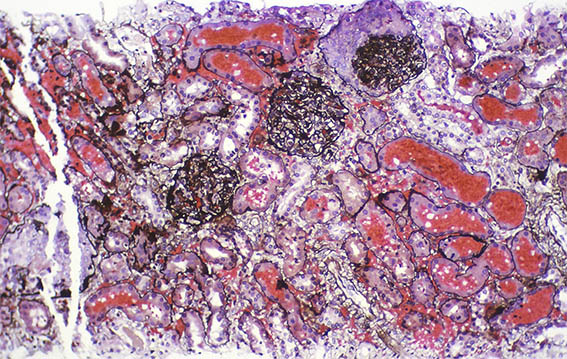

Figure 11. Methenamine-silver stain,

X400.

Figure 12. Immunohistochemistry for C4d (paraffin-emdedded tissue), X400.